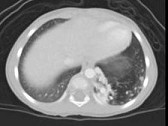

- 单项选择题女,2岁, 咳嗽,结合图像, 最可能的诊断是 ( )

A、先天性肺不张

B、细支气管肺炎

C、先天性支气管闭锁

D、先天性囊性腺瘤样畸形

E、肺隔离症